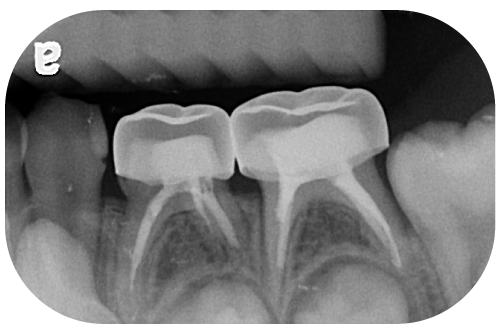

如果經拍攝 X 光片判斷後,發現小朋友 乳臼齒蛀牙 的範圍僅局限於牙齒的珐瑯質(牙釉質)上,此時如果清潔乾淨搭配定期塗氟,有機會使牙齒再礦化,讓原本蛀牙的地方有機會復原。

通常建議每三個月定期到診所,由牙醫師進行專業潔牙並搭配塗氟即可。